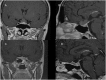

Objective: Rathke's cleft cysts (RCCs) are quite uncommon sellar lesions that can extend or even arise in the suprasellar area. The purpose of this study is to evaluate the effectiveness of both standard and extended endoscopic endonasal approaches in the management of different located RCCs.

Results: A standard transsphenoidal approach was used in 19 cases, while the extended variation of the approach in 10 cases (5 purely suprasellar and 5 intra-suprasellar RCC). Cysts contents was fully drained in all the 29 cases, whilst a gross total removal, that accounts on the complete cyst wall removal, was achieved in an overall 55,1% of patients (16/29), specifically 36,8% (7/19) that received standard approach and 90% (9/10) of those that underwent to extended approach. We reported a 56.2% of recovery from headache, 38.5% of complete recovery and 53.8% of improvement from visual field defect and an overall 46.7% of improvement of the endocrine functions. Postoperative permanent DI rate was 10.3%, overall post-operative CSF leak rate 6.9%; recurrence/regrowth occurred in 4 patients (4/29, 13.8%), but only one required a second surgery.

Conclusion: The endoscopic transsphenoidal approach for the removal of a symptomatic RCC offers several advantages in terms of visualization of the surgical field during both the exposure and removal of the lesion. The "extended" variation of the endoscopic approach provides a direct access to the supradiaphragmatic space, allowing adequate view and room for the safe removal of selected supradiaphragmatic RCCs, regardless of the sellar size (even a not enlarged sella), and provides a higher likelihood of preserving normal pituitary tissue and functions.